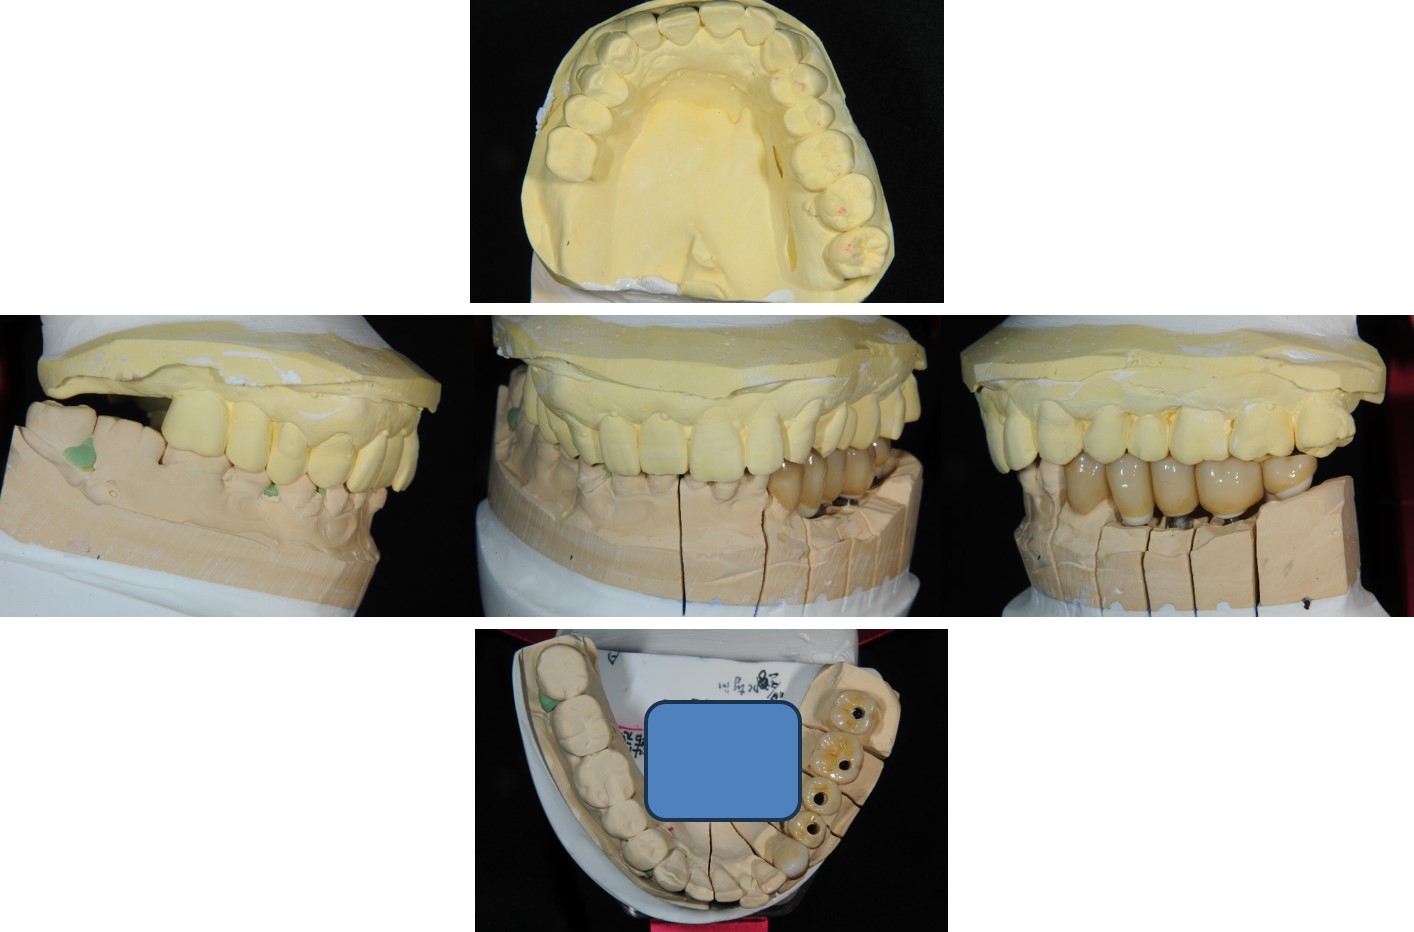

▼(下圖為蠟型復形,與電腦定位器,原來模型是這樣用的!)

▼接著還會用咬合器製作全瓷冠

蠟型復形,與電腦定位器

ImplantMax手術模板

咬合器製作全瓷冠